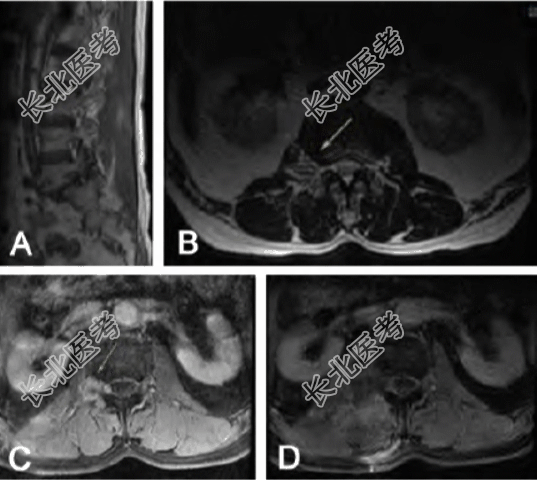

患者,男,67岁,因右下肢麻木半年余、右髂腰痛1个月余入院。既往无神经纤维瘤病、放疗、多发病灶、椎管外病灶等病史。入院体格检查:神志清楚,右髂腰部、下腰部压痛,腰部活动受限;右大腿前部麻木,感觉减退;右髂腰肌肌力3级,右股四头肌肌力3级,右胫前肌肌力3级,右腓肠肌肌力3级,右踇3级,右踇指跖屈肌肌力3级;病理征未引出。腰椎MRI平扫+增强示:腰2右侧椎旁见斑片样长T1、长T2信号,腰2椎管内见结节状信号影,经右侧椎间孔向椎旁延伸,明显不均匀强化,大小约1.9 cm×1.5 cm。术前诊断为右侧腰2椎管内外沟通型肿瘤(神经源性肿瘤可能)。全麻下行旁正中肌间隙入路椎管内外肿瘤切除术。术中见肿瘤呈实性,质地韧,边界清,无包膜,血供中等;显微镜下分块全切除肿瘤。术后病理示恶性周围神经鞘膜瘤(malignant peripheral nerve sheath tumor,MPNST),其中HE 染色显微镜下观察发现异型细胞呈卵圆形、短梭形,核分裂易见,瘤细胞呈巢状、束状分布,可见大片坏死,瘤组织呈浸润性生长;免疫组化结果显示CKpan(灶+)、CK20(-)、CK7(灶+)、villin(点灶+)、EMA(灶+)、Desmin(-)、SMA(-)、H-caldesmon(-)、Calponin(-)、STAT6(-)、S100(+)、SOX10(-)、Ki67(约60%+)、Bcl-2(-)。